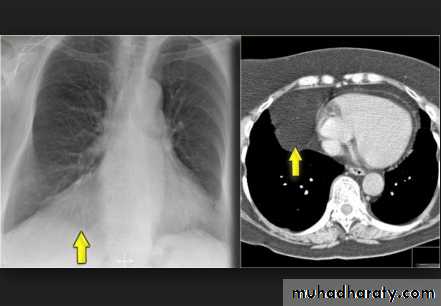

Subpulmonary pleural effusion. On the (A) erect PA and (B) lateral radiograph the effusion simulates a high hemidiaphragm. (C) Ultrasound and (D) CT clearly show that the effusion is located above the diaphragm. Arrows = diaphragmatic area.